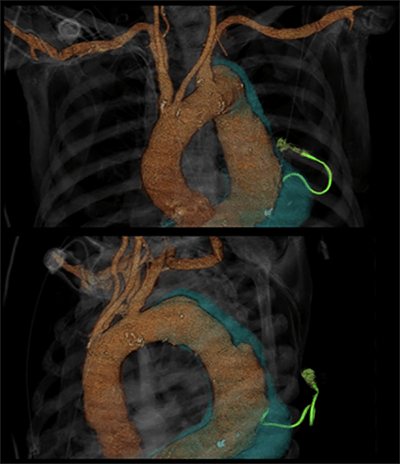

The patient is an 85-year-old male with a 7.9 cm extent I TAAA for which only open repair had been proposed. He and his family had elected against repair due to the severity of his many comorbid conditions and the high risk of the operation. His medical history is also significant for mild dementia, coronary artery disease, oxygen-dependent chronic obstructive pulmonary disease, recent pulmonary embolism (on rivaroxaban), and marginal zone lymphoma with mediastinal spread treated with palliative chemotherapy and radiation that was completed two weeks prior to the patient’s presentation to the referring hospital with dyspnea. Additionally, he had just completed antibiotic therapy for pneumonia and was found to have a fungal urinary tract infection at admission to the referring institution. Chest X ray (Figure 1) revealed a large left sided pleural effusion, presumed to be either malignant or parapneumonic, for which a 7-French pleural pigtail catheter was placed through a posterior approach under CT guidance.

Figure 1. Left sided pleural effusion visible on chest radiograph

Upon placement, there was immediate brisk and bright red blood return from the catheter as well as transient hypotension that responded to a saline bolus. The catheter was clamped, and a post-procedure non-contrasted CT of the chest confirmed catheter placement within the aneurysm sac of his known TAAA. The patient remained hemodynamically stable after the initial transient drop in blood pressure and was transferred emergently to our institution. A 1 mm slice CTA was obtained for better anatomical detail, three-dimensional reconstruction, and centerline measurements in the event that aortic repair would be required (Figure 2 and Figure 3). At the site of chest wall entry, the aneurysm sac was immediately adjacent to the posterior chest wall. The catheter was primarily traversing organized, mural thrombus, but the curved distal tip was just within the patent lumen.

Figure 3. 3-dimensional reconstruction of CTA in coronal and oblique views demonstrating the catheter within the TAAA